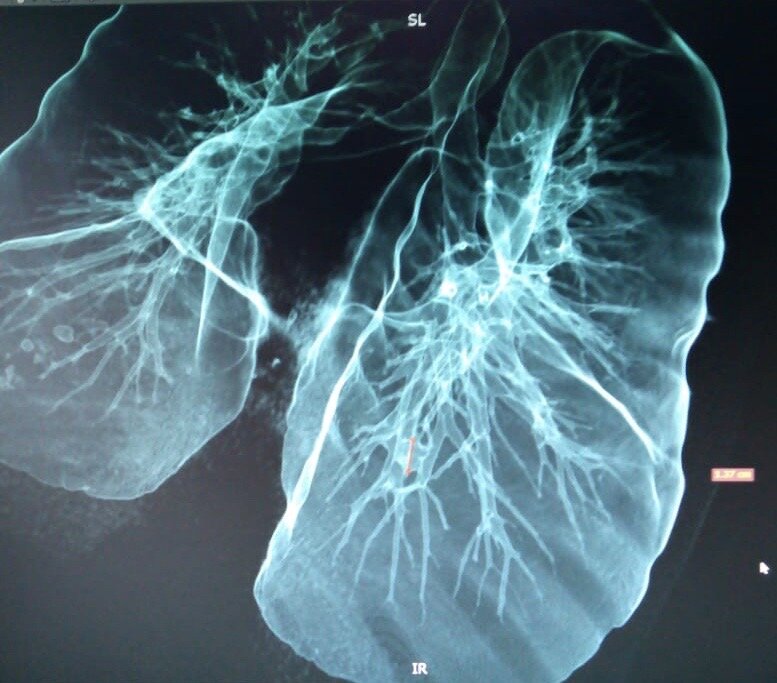

В большинстве случаев компьютерную томографию легких и бронхов проводят без использования контрастного вещества. В течение нескольких секунд сканирования томограф делает множество снимков грудной клетки с шагом, не превышающим 1 мм. Все сканы передаются на компьютер, который формирует из них трехмерное изображение исследуемого органа или участка тканей. Такая методика характеризуется достаточной информативностью и позволяет выявить практически все патологии на первых стадиях развития.

Введение контрастирующего вещества необходимо для оценки злокачественного потенциала в грудной клетке: в сердце, легких и средостении. По принципу накопления контраста рентгенолог может с высокой точностью диагностировать наличие онкологических заболеваний даже на самой ранней стадии их развития. КТ легких с контрастированием позволяет провести дифференциальную диагностику мелкоклеточного и немелкоклеточного рака.

• 3D изображение тканей;

• максимальная информативность;

• возможность точного определения локации, размера и характера патологического очага;

• отсутствие слепых зон, позволяющее оценить состояние всех сегментов;

• возможность выявления новообразований на начальных этапах их развития с размером до 5 мм.